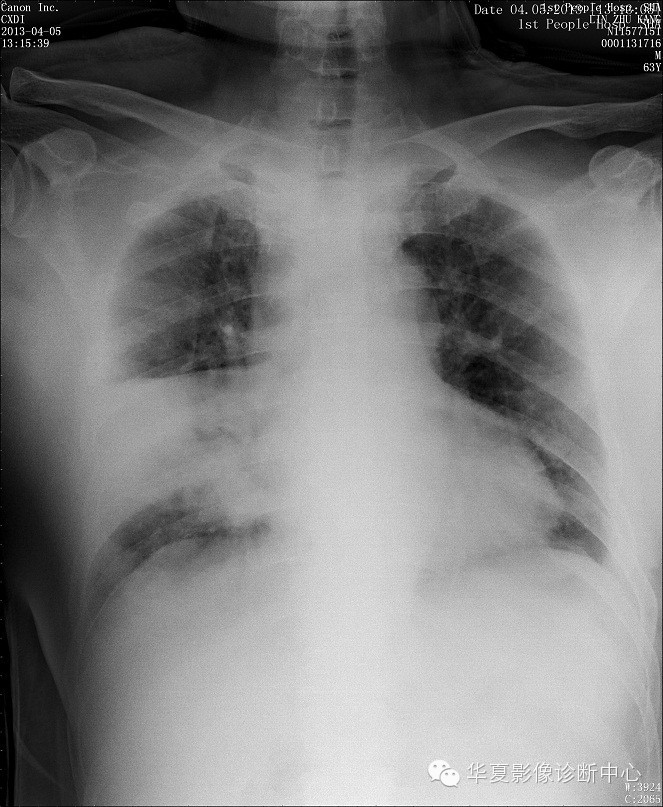

【病例学习】甲型H7N9禽流感一例

男性 63

发热咳嗽5天

2013-4-5拍片示右肺实变,收入院,追问病史,发病期间肌肉酸痛,头痛,无腹痛腹泻,无明显胸闷气急,无意识改变。有高血压病史,无其它病史。

2013-4-7CT进一步检查。

最终诊断:H7N9。